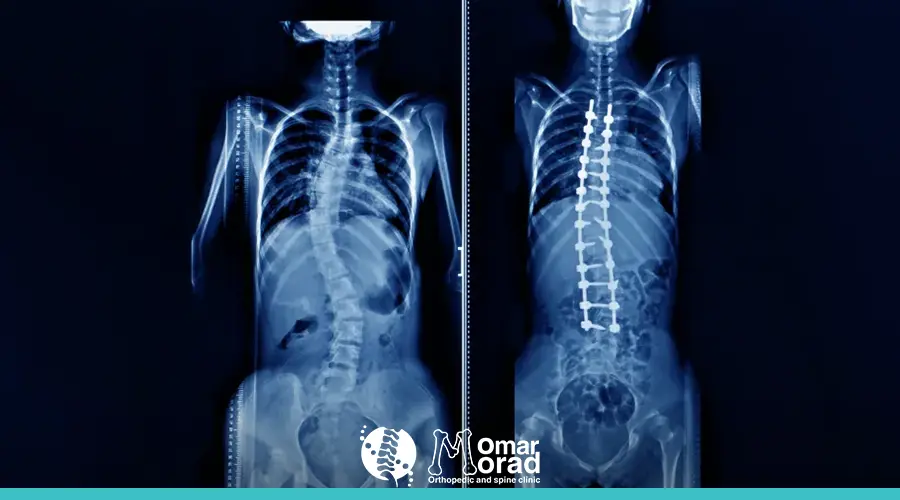

2. الأشعة السينية: تعد الأشعة السينية من أفضل الطرق لتحديد درجة الاعوجاج في العمود الفقري.

4. الجراحة:

• في حالات اعوجاج العمود الفقري الشديدة، قد تكون الجراحة ضرورية لتقويم العمود الفقري وإصلاح التشوهات.

• أفضل دكتور جراحة عمود فقري في مصر قد يوصي بإجراء عملية دمج الفقرات أو تركيب أجهزة معدنية لتثبيت العمود الفقري.

الجراحة غالبًا ما تكون الخيار الأخير بعد فشل العلاجات غير الجراحية. يمكن أن تشمل جراحة اعوجاج العمود الفقري إجراءات مثل:

• دمج الفقرات: يتم خلالها دمج فقرتين أو أكثر معًا باستخدام أدوات خاصة لتثبيت العمود الفقري.

• إعادة تصحيح العمود الفقري: إعادة العمود الفقري إلى وضعه الطبيعي باستخدام تقنيات حديثة مثل الأسلاك المعدنية أو الأقواس.